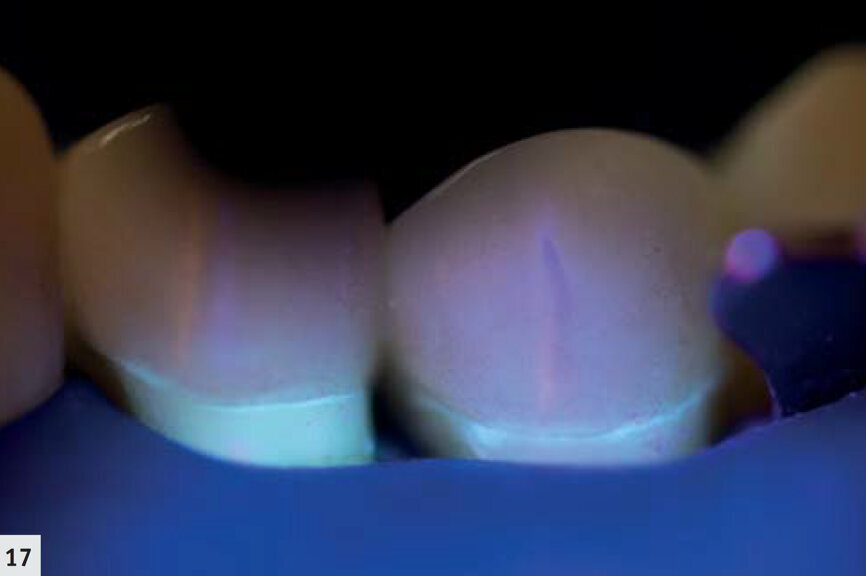

Fig. 17 : Même onlay que sur la Fig. 16, après polymérisation. Seule une très fine ligne correspondant au scellement est visible ; l’absence d’un surplomb est confirmée.

La majorité des résines composites émettent une hyperfluorescence sous le rayonnement proche-UV.6, 7 Les autres restaurations, minimes, peuvent facilement être observées en mode détection (Fig. 14). De cette façon, il est possible de déceler la présence d’un surplomb et de définir plus aisément les espaces marginaux (Fig. 15). L’élimination des restaurations défectueuses devient ainsi beaucoup plus facile et s’effectue sans retrait inutile de tissu dentaire sain. De plus, ce mode représente un outil très utile au cours des techniques de scellement ; les excès de ciment résine sont immédiatement détectés et peuvent donc être éliminés (Fig. 16) sans polymérisation simultanée ; après le nettoyage, le même dispositif peut être utilisé pour polymériser les limites marginales (Fig. 17). Au cours du suivi, les restaurations sont mieux visualisées (Figs. 18–19) et il est possible d’examiner rapidement et complètement leurs limites marginales.